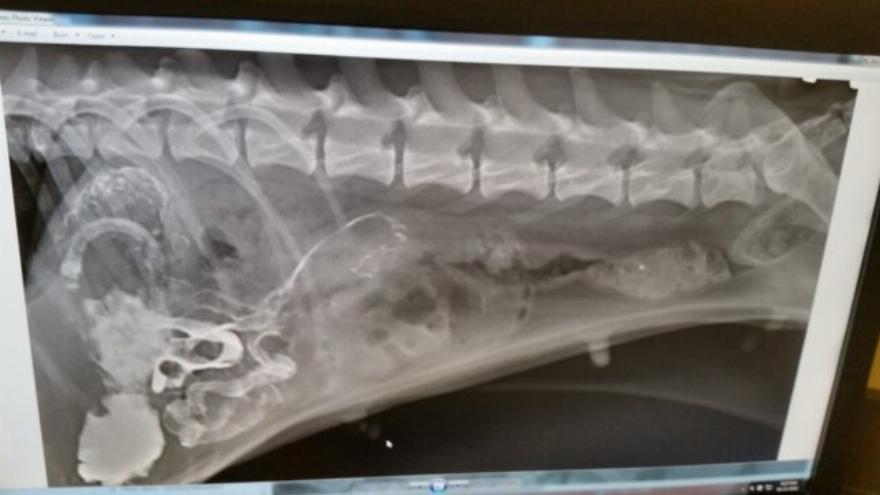

“Οι ακτινογραφίες δεν μας έδειξαν αυτό που θέλαμε να δούμε. Το μικρό της σώμα απέρριπτε τα πάντα. Ο κτηνίατρος της έκανε κλύσμα με ζεστό νερό ενώ περιμέναμε στο δωμάτιο. Πέρασαν τριάντα λεπτά και ο γιατρός επέστρεψε μόνο για να μας πει ότι θα χρειαζόταν χειρουργική επέμβαση. Ο γιατρός δεν μπορούσε να μας δώσει πιθανότητες επιβίωσης μετά το χειρουργείο. Είπε ότι αφού θα έμπαιναν στα τυφλά, δεν θα ήξεραν.”

“Το άδειο κλουβί της στο διαμέρισμα βάραινε τις καρδιές μας, αλλά ξέραμε ότι οι χειρουργοί θα την φρόντιζαν καλά. Σήμερα το μεσημέρι λάβαμε ένα τηλεφώνημα ότι η επέμβαση ήταν επιτυχής! Έπρεπε να κόψουν το έντερό της σε πέντε διαφορετικά σημεία για να αφαιρέσουν όλα τα υφάσματα και τα πλαστικά που είχε φάει προσπαθώντας να επιβιώσει μόνη της. Τώρα βρίσκεται σε ανάρρωση και μας είπαν ότι ίσως μπορέσουμε να την πάρουμε σπίτι την Πέμπτη. Ανυπομονούμε να την έχουμε και πάλι μαζί μας”.